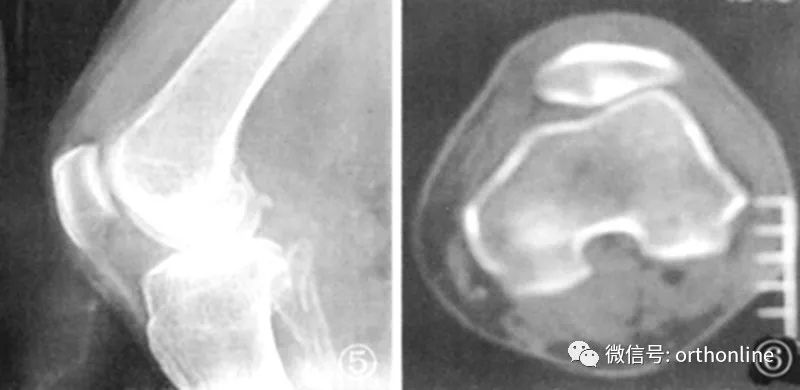

髌骨软骨软化平片及CT表现:膝关节侧位片示关节间隙变窄, 关节缘皮质线有中断。CT示髌股关节略有错位,关节间隙变窄,软骨下骨质密度增高